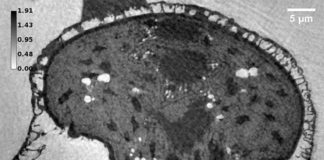

Las mitocondrias desempeñan un papel fundamental en la supervivencia de las células neuronales y en su muerte, ya que regulan el metabolismo energético y la muerte celular, actuando como la batería de las células.

Se han identificado anormalidades mitocondriales en muchos tipos de células en el Alzheimer, con déficits que tienen lugar antes del desarrollo de las agregaciones patológicas clásicas. Los cambios energéticos han sido hallados en muchos tipos diferentes de células en pacientes de esta enfermedad. Se cree que este es uno de los primeros cambios que tienen lugar en las células cerebrales, quizás incluso antes de que los síntomas sean percibidos por los enfermos.

Esta investigación innovadora también ha tenido un efecto colateral: el medicamento cambió la forma de las mitocondrias al redistribuir la proteína 1 relacionada con la dinamina (Drp1) a las mitocondrias en las células cutáneas de personas con Alzheimer. Drp1 es un regulador de la forma mitocondrial y se localiza en la mitocondria para iniciar eventos de fisión. Se cree que esto podría tener efectos neuroprotectores en la enfermedad de Alzheimer. Este estudio sugiere que esta vía podría ser explorada por fármacos que ya tienen esos efectos.